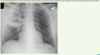

Which rib?

Posterior aspect of right 6th rib